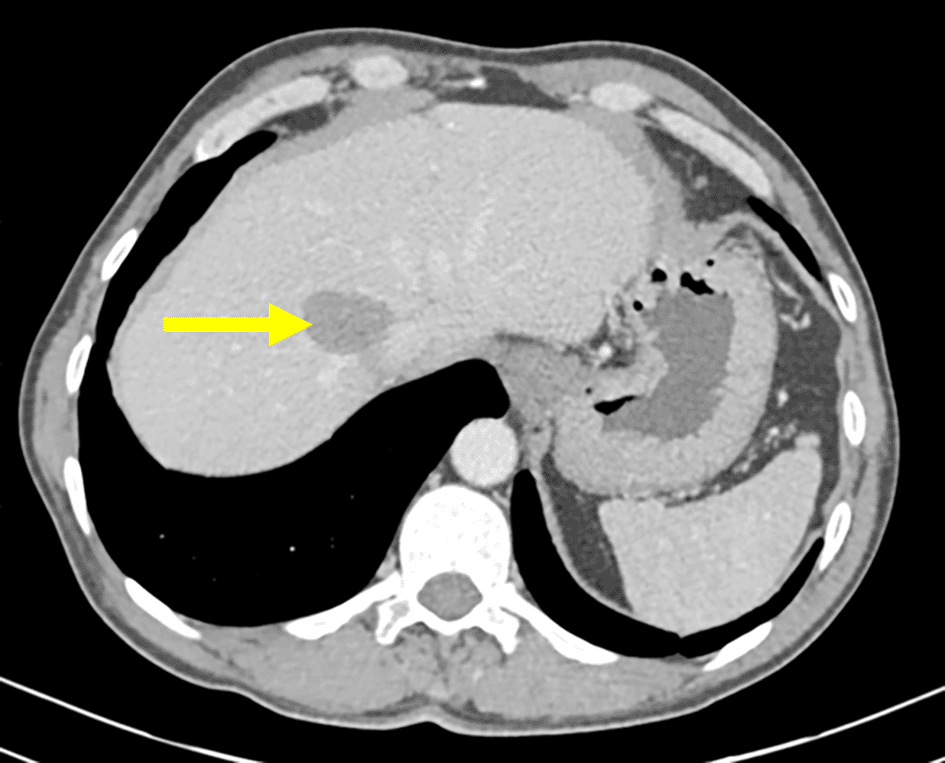

The patient was followed up at the department of abdominal surgery for a multiple organ hydatidosis including 13 hydatid cysts: the lungs, the liver ( Figure 1), the left heart ventricle, the left kidney (Figure 2), the abdomen cavity, the muscles (psoas, adductors), and the subcutaneous gluteal area. The majority of these cysts were already treated surgically and some of them are scheduled to be removed (Table 1). The patient has received oral Albendazole 400 mg twice-daily for 2 years.

The annual incidence of hydatidosis is 11.3 per 100000 inhabitants.1 Usually, hydatidosis presents as a single cyst involving the liver or the lungs, but multiple organs may be affected in some cases. In our case we are reporting multiple atypical locations including the heart, the kidney, the muscles, and the subcutaneous tissue. The simultaneous coexistence of cysts in these locations simultaneously has not been described in the literature. In the present paper, focus was not put on the liver and the lungs as they are the classic location of this parasitosis, and they are commonly reported in the literature. It was rather put on the other locations.

Heart involvement is uncommon and accounts for less than 0.5% of the cases, it is usually a part of disseminated infection.3 This localization is potentially fatal without surgical treatment but thanks to the improvement in surgical techniques, its morbidity has declined drastically. The patient underwent open heart surgery to remove a left ventricular wall cyst. Post-surgical echocardiography revealed no local recurrence and no abnormalities.

Invasion of the myocardium usually occurs hematogeniously through the coronary arteries and since the majority of the population have a left dominant circulation, the left ventricle is the most commonly involved part of the heart (60%),4 Another possible explanation is the dissemination from the lungs either following a pulmonary vein rupture and migration of the cysts5 or by a direct contact with hydatid cysts originating from the lung.6